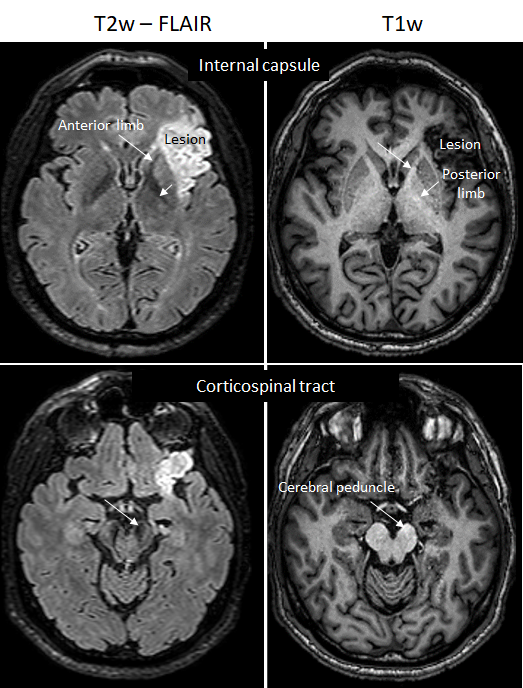

La création d’un modèle lésionnel comportant une hyperactivation des NMDA a permis de tester la capacité de la [18F] FNM à discriminer une zone d’hyperactivation d’une zone normale. Ce modèle a été réalisé sur des rats qui ont subit une injection intracérébrale d’excitotoxines agonistes du glutamate, provoquant une suractivation des récepteurs au glutamate et spécifiquement du récepteur NMDA. Cette expérimentation nous a permis d’évaluer la capacité du radiotraceur à discriminer une hyperactivation des récepteurs NMDA par comparaison de l’hémisphère sain et de l‘hémisphère lésé.

Nous avons pu ainsi visualiser la cinétique des activations de récepteurs NMDA après lésion (J0, J+1, J+3, J+5). Grâce au traitement d’image et à l’analyse voxel à voxel sur le logiciel spm , nous avons fait un « template » de cerveaux de rats sain et nous avons pu comparer les rats lésés à ce template. Nous avons pu constater que l’on pouvait discerné la zone lésée avec la FMN mais que les zones hyperactives évoluent avec le temps avec une activation importante de la zone perilesionnelles précoce et une activation de zones en réseaux avec la zone lésé plus tardive.